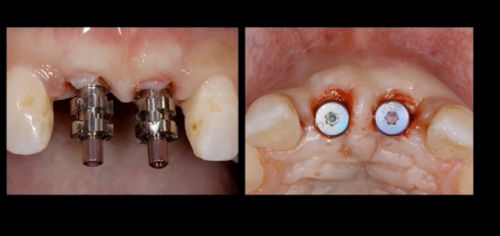

Фото. Удаление 11, 21 зубов из-за большой потери твердых тканей зубов.

Фото. Внедрены 2 имплантата в области 11, 21 зубов.

Фото. Фиксированы трансферы для снятия оттисков и изготовления временных реставраций.